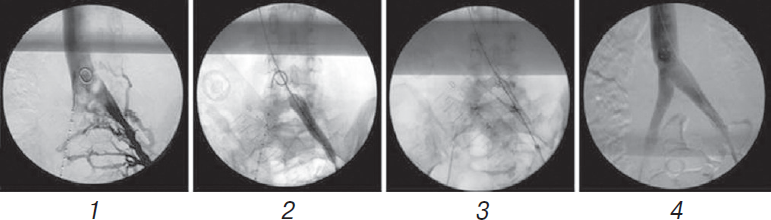

Лечение синдрома компрессии левой общей подвздошной вены (синдрома Мея – Тюрнера) в основном проводят рентгенохирургически, оно включает в себя следующие этапы (рис. 13) [49]:

- периоперационную флебографию, как правило, показывающую коллатеральное кровообращение левой общей подвздошной вены под правой общей подвздошной артерией;

- баллонную венопластику левой общей подвздошной вены;

- установку стента в левую общую подвздошную вену;

- контрольную флебографию, показывающую проходимость обеих общих подвздошных вен и отсутствие коллатерального кровообращения.

Рис. 13. Эндоваскулярное лечение синдрома компрессии левой общей подвздошной вены: 1 — периоперационная флебография; 2 — баллонная венопластика; 3 — установка стента в левую общую подвздошную вену; 4 — контрольная флебография

M.D. Bomalaski et al. (1993) описали необычный случай варикоцеле у молодого человека вследствие синдрома компрессии левой общей подвздошной вены. Варикоцеле было вызвано венозными коллатералями и было устойчиво к хирургической перевязке яичковой вены. Этот случай иллюстрирует необходимость отказа от стандартной хирургической техники в подобных ситуациях [50]. 28.03.2017 в Городской клинической больнице им. Е.О. Мухина г. Москвы пациенту 38 лет с рецидивным двусторонним варикоцеле (5 операций в анамнезе), болями в области таза, эректильной дисфункцией и варикозной болезнью вен органов малого таза при синдроме Мея – Тюрнера впервые была выполнена операция — рентгенэндоваскулярная ангиопластика и стентирование левой общей и левой наружной подвздошных вен с положительным эффектом (рис. 14) [51].

Рис. 14. В.Ф. Харпунов, Р.Э. Мамедов, А.А. Капто. Городская клиническая больница им. Е.О. Мухина. Первая баллонная ангиопластика и стентирование левой общей подвздошной и левой наружной подвздошных вен мужчине с синдромом Мея – Тюрнера и варикозной болезнью вен органов малого таза

Выраженная тазовая симптоматика на фоне рецидивного варикоцеле, наличие компрессии подвздошных сосудов и коллатерального кровообращения, по данным флебографии, служили признаками илеопельвикальной венной гипертензии и определили показания к ангиопластике и стентированию левой общей подвздошной вены. Оперативное лечение синдрома подвздошной венозной компрессии включало в себя следующие этапы: 1) пункцию вены (бедренной, подколенной, яремной) под контролем УЗИ; 2) мультипроекционную интраоперационную флебографию, показывающую коллатеральное кровообращение левой подвздошной вены; 3) баллонную ангиопластику левой подвздошной вены; 4) имплантацию одного стента в левую подвздошную вену; 5) постдилятацию стентированного сегмента; 6) контрольную флебографию, показывающую проходимость левой подвздошной вены и отсутствие коллатерального кровообращения. Послеоперационное ведение больного включало в себя: 1) антикоагулянтную терапию — ривароксабан 20 мг в сутки — 6 месяцев после операции; 2) ультразвуковое ангиосканирование подвздошных сосудов в 1-е сутки, через 2 недели и через 1, 3, 6 месяцев после операции. В ближайшем послеоперационном периоде (в течение часа) жалобы на боли в области малого таза практически исчезли, а через неделю после операции пациент отметил восстановление эрекции без какой-либо специфической терапии. Результат оказался стойким в течение 10 месяцев наблюдения.